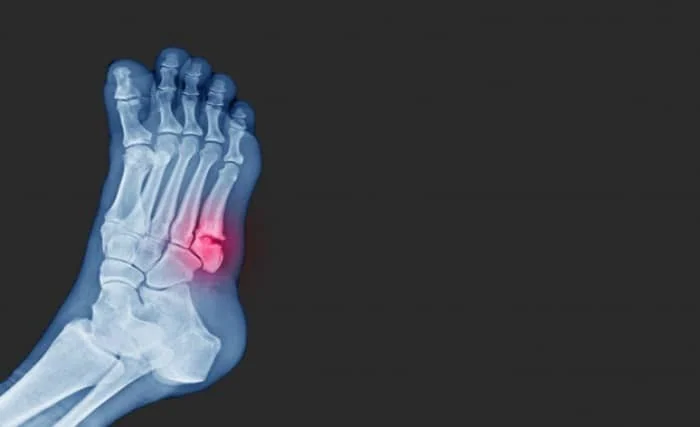

شکستگی کنده شده :

عضلات با استخوان تاندون که  نوعی بافت همبند است ، به استخوان لنگر می اندازند . انقباضات عضلانی قدرتمند می تواند تاندون را از بین ببرد و قطعات آن را بیرون بکشد . این نوع شکستگی بیشتر در مفاصل زانو و شانه دیده می شود .